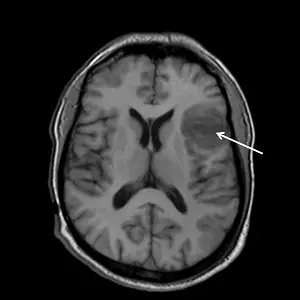

中風男性的核磁共振影像如下圖所示,最有可能的診斷為何?

- 觀察腦室內的腦脊髓液 (CSF) 呈現黑色(低訊號),腦灰質訊號比白質稍暗,這是典型的 T1 加權影像 (T1-weighted image)。

- 影像右側(即病人的左腦半球)可見一個大範圍的明顯低訊號 (Hypointense) 區域(白色箭頭所指)。

- 該病灶範圍涵蓋了外側的額葉與頂葉皮質區,並向深部延伸至基底核 (Basal ganglia) 與腦島 (Insula) 區域。

- 此區域完全符合中大腦動脈 (Middle Cerebral Artery, MCA) 的典型供血範圍。

- 病灶呈現低訊號,代表該區腦組織發生水腫或壞死(Infarction/Edema),符合缺血性中風的表現。